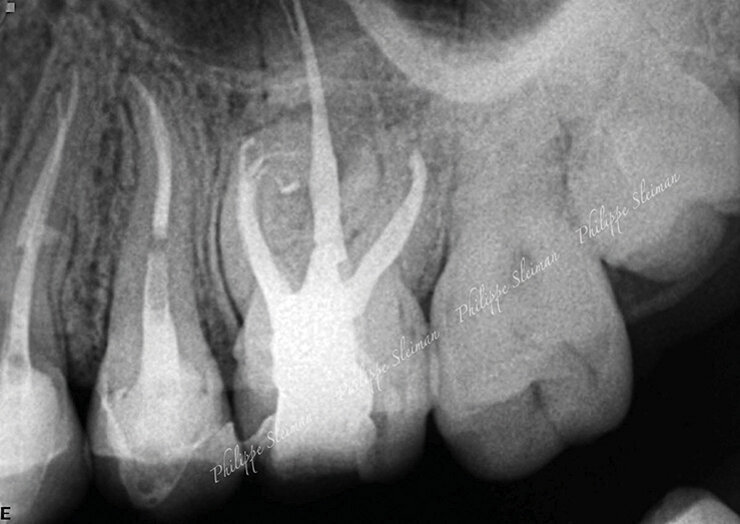

Slučaj 3 – Slika br. 7: Inicijalni periapikalni Rtg snimak

Slučaj 3 – Slika br. 11: Periapikalni kontrolni Rtg snimak 18 meseci nakon tretmana

Poslednji slučaj o kome bih želeo da govorim u ovom članku, jedan je od najizazovnijih tretmana. Pacijentkinja je upućena iz inostranstva na remont gornjeg molara jer je insistirala na spasavanju zuba. Na malom rendgenskom snimku (Slika br. 6) sam jasno video da imamo separisan instrument u mezijalnom korenu, ali je anatomija bila veoma sumnjiva. Pacijentkinja mi je dala CD sa CBCT urađenim za nju, i gledajući različite delove , mada bih više voleo veću rezoluciju snimka (Slika br. 7), primetio sam 3 različita izlaza za mezijalni koren sa veoma neobičnom anatomijom. Proučavajući ovaj slučaj primetio sam i grananje na palatinalnom korenu u apikalnoj oblasti. Objasnio sam pacijentkinji da ću dati sve od sebe da joj spasem zub. Koristio sam istu sekvenca turpija Traverse i Zenflex u distalnom i palatalnom kanalu korena zuba do pune radne dužine, a kod mezijalnog korena sam dostigao do zalomlejnog instrumenta i prešao na veoma delikatan zadatak njegovog zaobilaženja i obrade ovog veoma složenog sistema korenskih kanala. Slika br. 8 prikazuje neposrednu postoperativnu i 3D obturaciju mezijalnog kompleksa, kao i palatinalno grananje. Slike br. 9 i 10 su nakon 12 i 18 meseci od tretmana gde se vidi dobro zarastanje i svaki put kada uzmem da pogledam iz drugačijeg ugla vidim složenost mezijalnog korena.